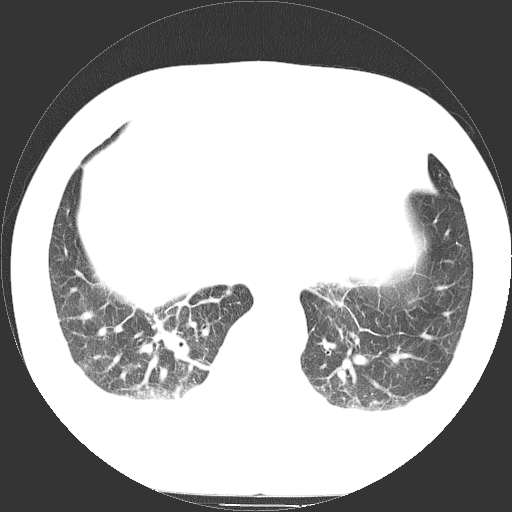

标题: CT21804:男,65岁,咳嗽、咳痰、发热5天。 [打印本页]

男,65岁,咳嗽、咳痰、发热5天。

慢支 肺间质纤维化合并感染!

支气管扩张合并感染,胸膜肥厚

考虑慢支并感染,肺间质纤维化。

两肺间质性炎症并感染

两肺间质纤维化,支扩合并感染,双侧胸腔积液